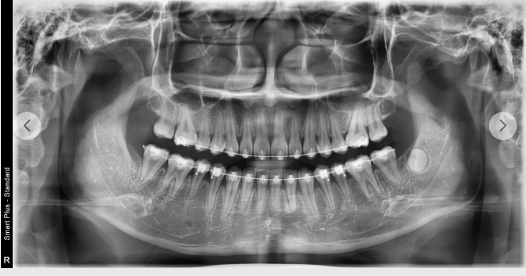

(부정교합 교정 치료 전(위)/후(아래))